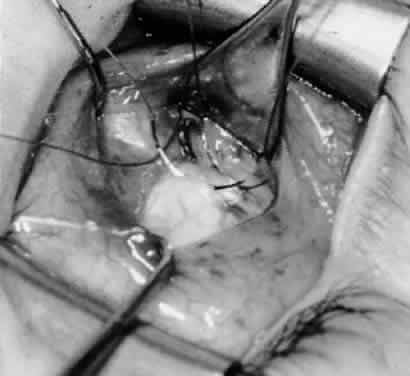

Fig. 14. The inferior temporal vortex vein, 8 mm posterior to the temporal insertion of the inferior rectus muscle, is held on a Green muscle hook.

Fig. 15. The placement of sutures within the sclera for a recession procedure of 10 mm. The anterior suture is placed 3 mm temporal and 2 mm posterior to the lateral insertion of the inferior rectus muscle, and the posterior suture is placed 3 mm further posteriorly.

Fig. 16. Two sutures straddle the inferior temporal vortex vein insertion for a 14-mm recession procedure.

Fig. 17. Knots are tied to show the placement. The inferior oblique muscle is held on a Stevens muscle hook.